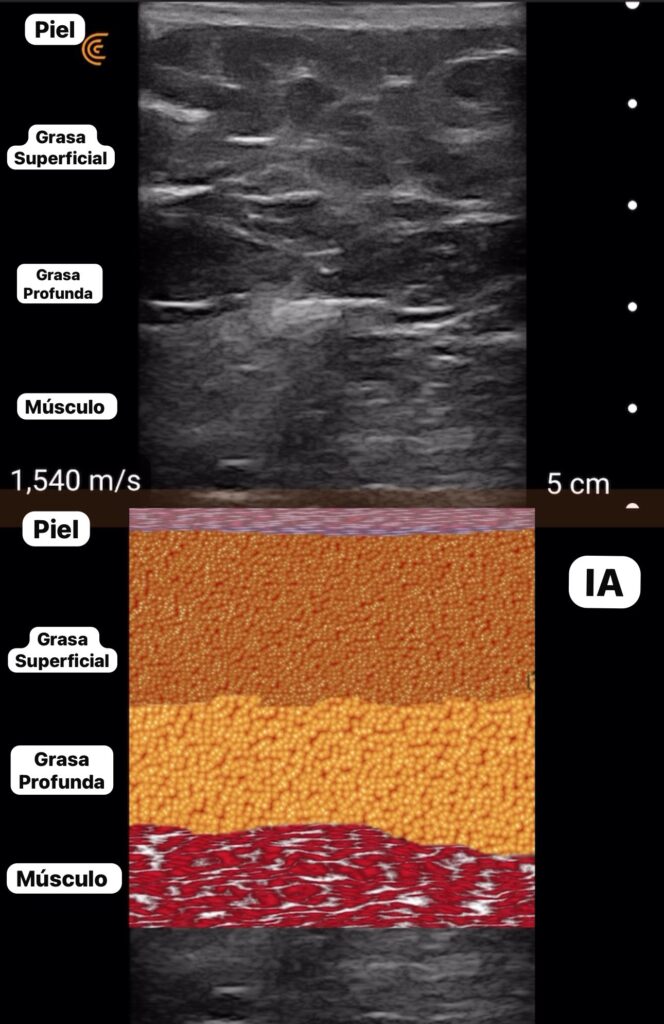

A partir de este año, por medio de una empresa que se llama Clarius, se añadió inteligencia artificial a estos dispositivos. Ahora estamos viendo unas imágenes con este ecógrafo donde se puede identificar el plano muscular y el plano graso y por ende no vas a tener riesgo de colocar grasa en músculo y vas a evitar muerte en tus pacientes.

Diferencia entre la ecografía tradicional y con ayuda de la inteligencia artificial.                     /FOTO: CORTESÍA.

Esto es histórico porque nunca antes en la ecografía se habían visto imágenes tan precisas y a color como ahora y esto es gracias a la inteligencia artificial.

Desafortunadamente no, Estados Unidos es el primer país que soporta esa inteligencia artificial que funciona en vivo, o sea, yo coloco el ecógrafo y la inteligencia artificial me va a convertir la imagen del ecógrafo tradicional a una imagen a color. La idea es llevar esa tecnología a Colombia y a Valledupar, eso es lo que estamos trabajando.